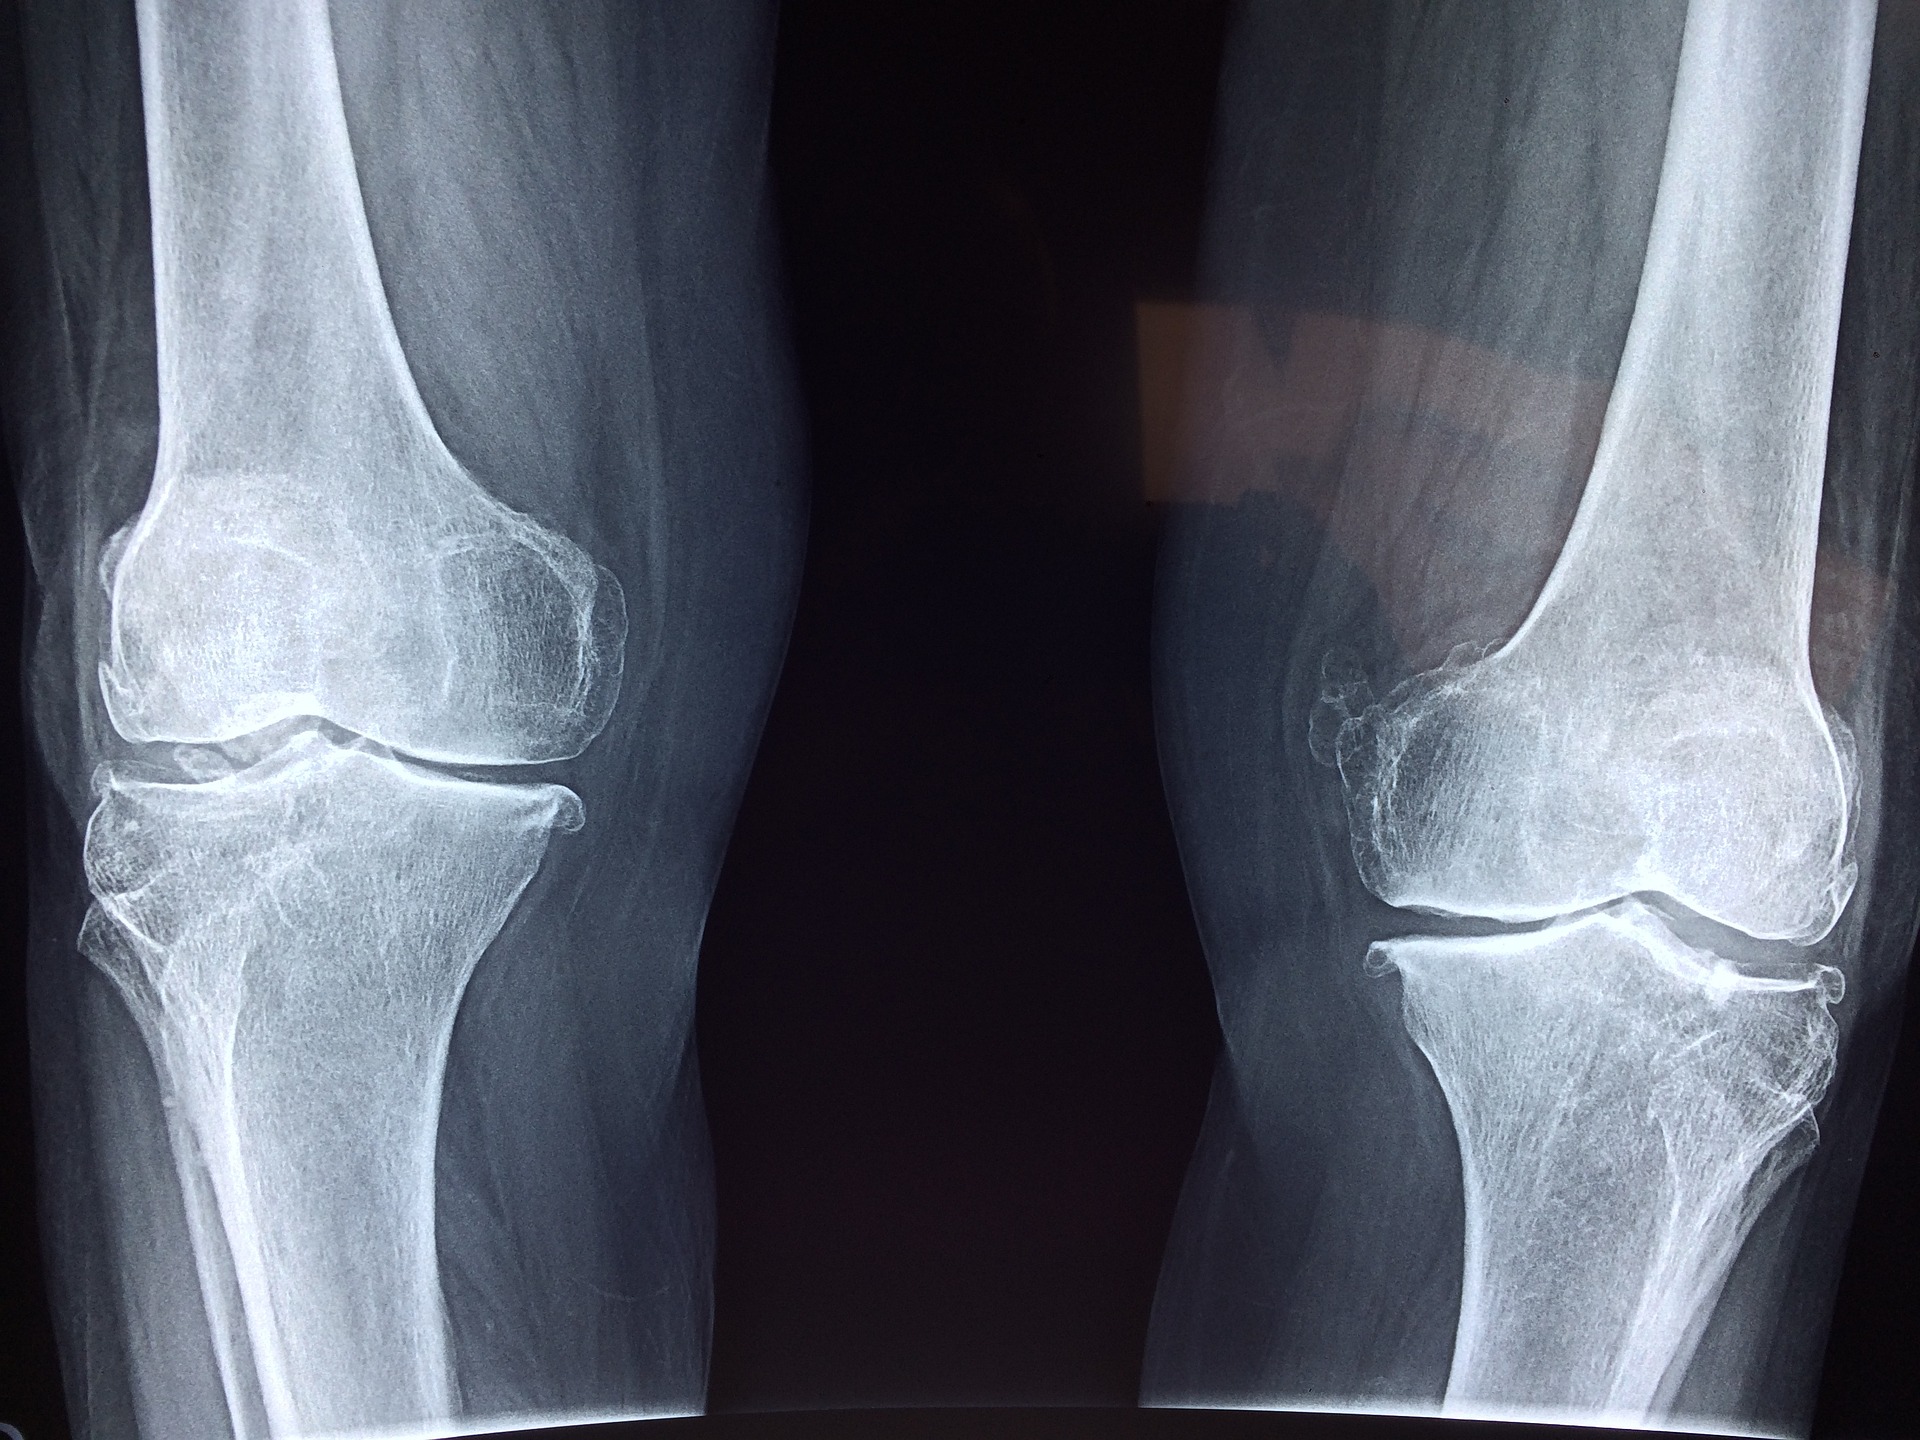

고갈된 뼈조직을 재생하기 어려워지는 질환으로, 뼈의 밀도가 감소하여 뼈가 쉽게 파괴되는 증상이 일어납니다. 골다공증은 주로 50세 이상의 여성에서 발생하는데, 여성호르몬 수치의 감소가 원인 중 하나입니다. 일반적으로 골다공증의 초기 증상은 증상이 없으며, 골밀도 감소로 인한 골절 위험이 크게 높아집니다.

골밀도 검사 : 골밀도 검사는 골다공증 진단과 예방에 중요한 검사입니다. 골밀도 검사를 통해 뼈의 밀도를 측정하여 골다공증 위험을 파악할 수 있습니다.